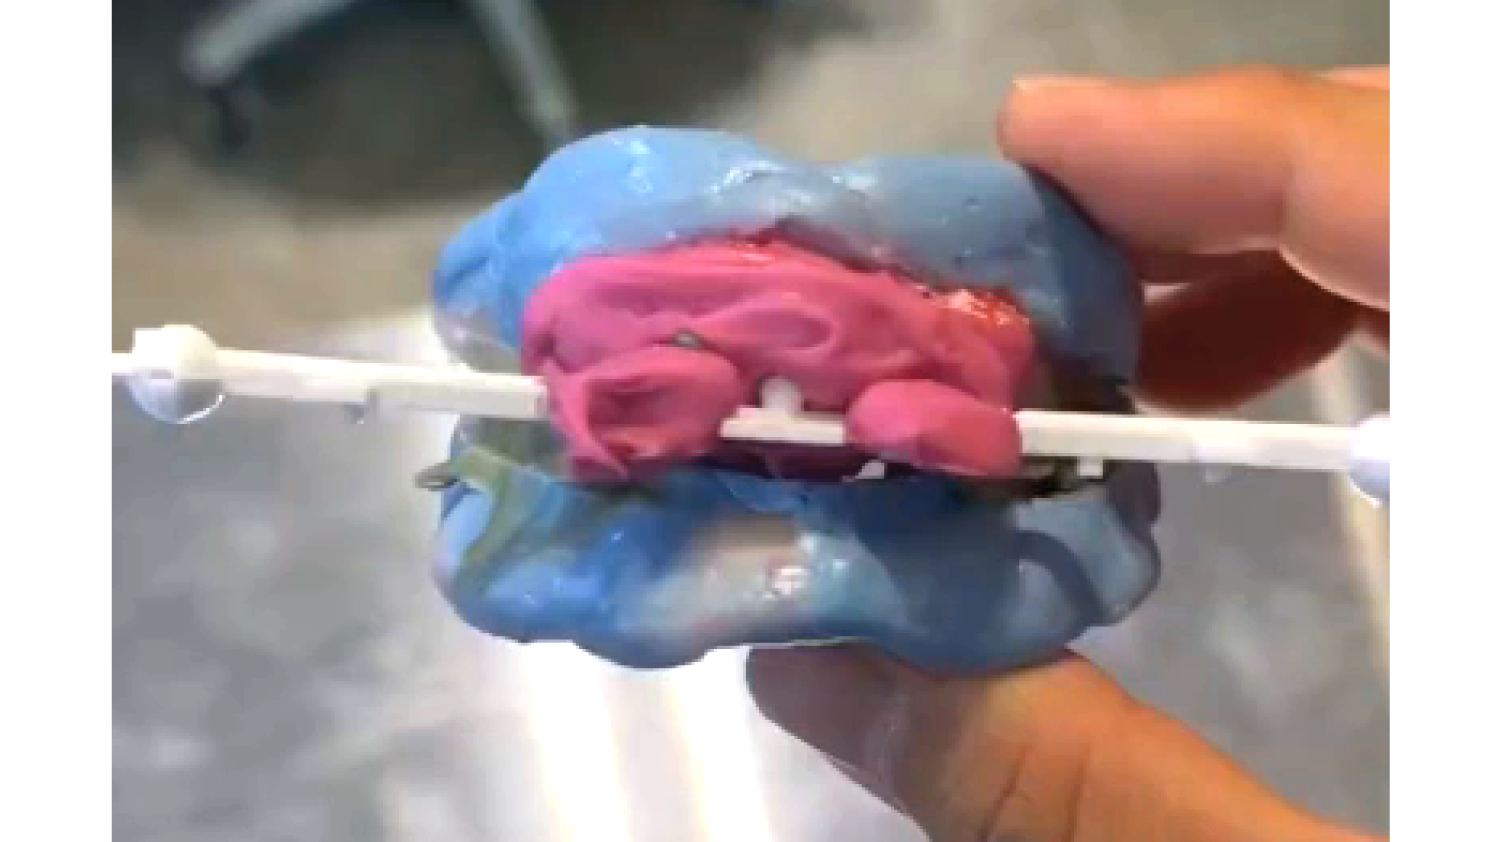

Course Overview

This course presents simplified yet clinically precise workflows for edentulous patients, enhancing both efficiency and patient comfort. Using the JB Tray, participants will learn how to combine custom tray fabrication, final impression, and jaw relation records in a single appointment, supported by digital processing and a live demonstration.

The program also introduces the JB Fork system, which integrates CBCT imaging and anterior reference points to enable one-step surgical stent fabrication without repeated impressions. Through practical demonstrations, attendees will see how this approach streamlines implant surgery while maintaining accuracy. The course concludes with insights into plasma surface treatment in implantology, highlighting its role in advancing clinical outcomes.

• Old and New in Complete Denture Procedures: From Custom Tray Fabrication to Final Impression and Jaw Relation – All in One Visit!

• Optimal Combination of JB Tray and Digital Denture Workflow.

Course Overview

This course presents simplified yet clinically precise workflows for edentulous patients, enhancing both efficiency and patient comfort. Using the JB Tray, participants will learn how to combine custom tray fabrication, final impression, and jaw relation records in a single appointment, supported by digital processing and a live demonstration.

The program also introduces the JB Fork system, which integrates CBCT imaging and anterior reference points to enable one-step surgical stent fabrication without repeated impressions. Through practical demonstrations, attendees will see how this approach streamlines implant surgery while maintaining accuracy. The course concludes with insights into plasma surface treatment in implantology, highlighting its role in advancing clinical outcomes.

• Old and New in Complete Denture Procedures: From Custom Tray Fabrication to Final Impression and Jaw Relation – All in One Visit!

• Optimal Combination of JB Tray and Digital Denture Workflow.

Course Curriculum

Part 1

One-Step Denture with JB Tray

• Fundamentals of jaw relation records in edentulous patients: Determining VD, CR, and the occlusal plane

• The concept of closed-mouth impression and understanding the appropriate external form of dentures

• One-step clinical workflow with the JB Tray: From custom tray fabrication to final impression and jaw relation record in a single appointment

• Digital processing of impressions obtained with the JB Tray

• Live demonstration with an edentulous patient